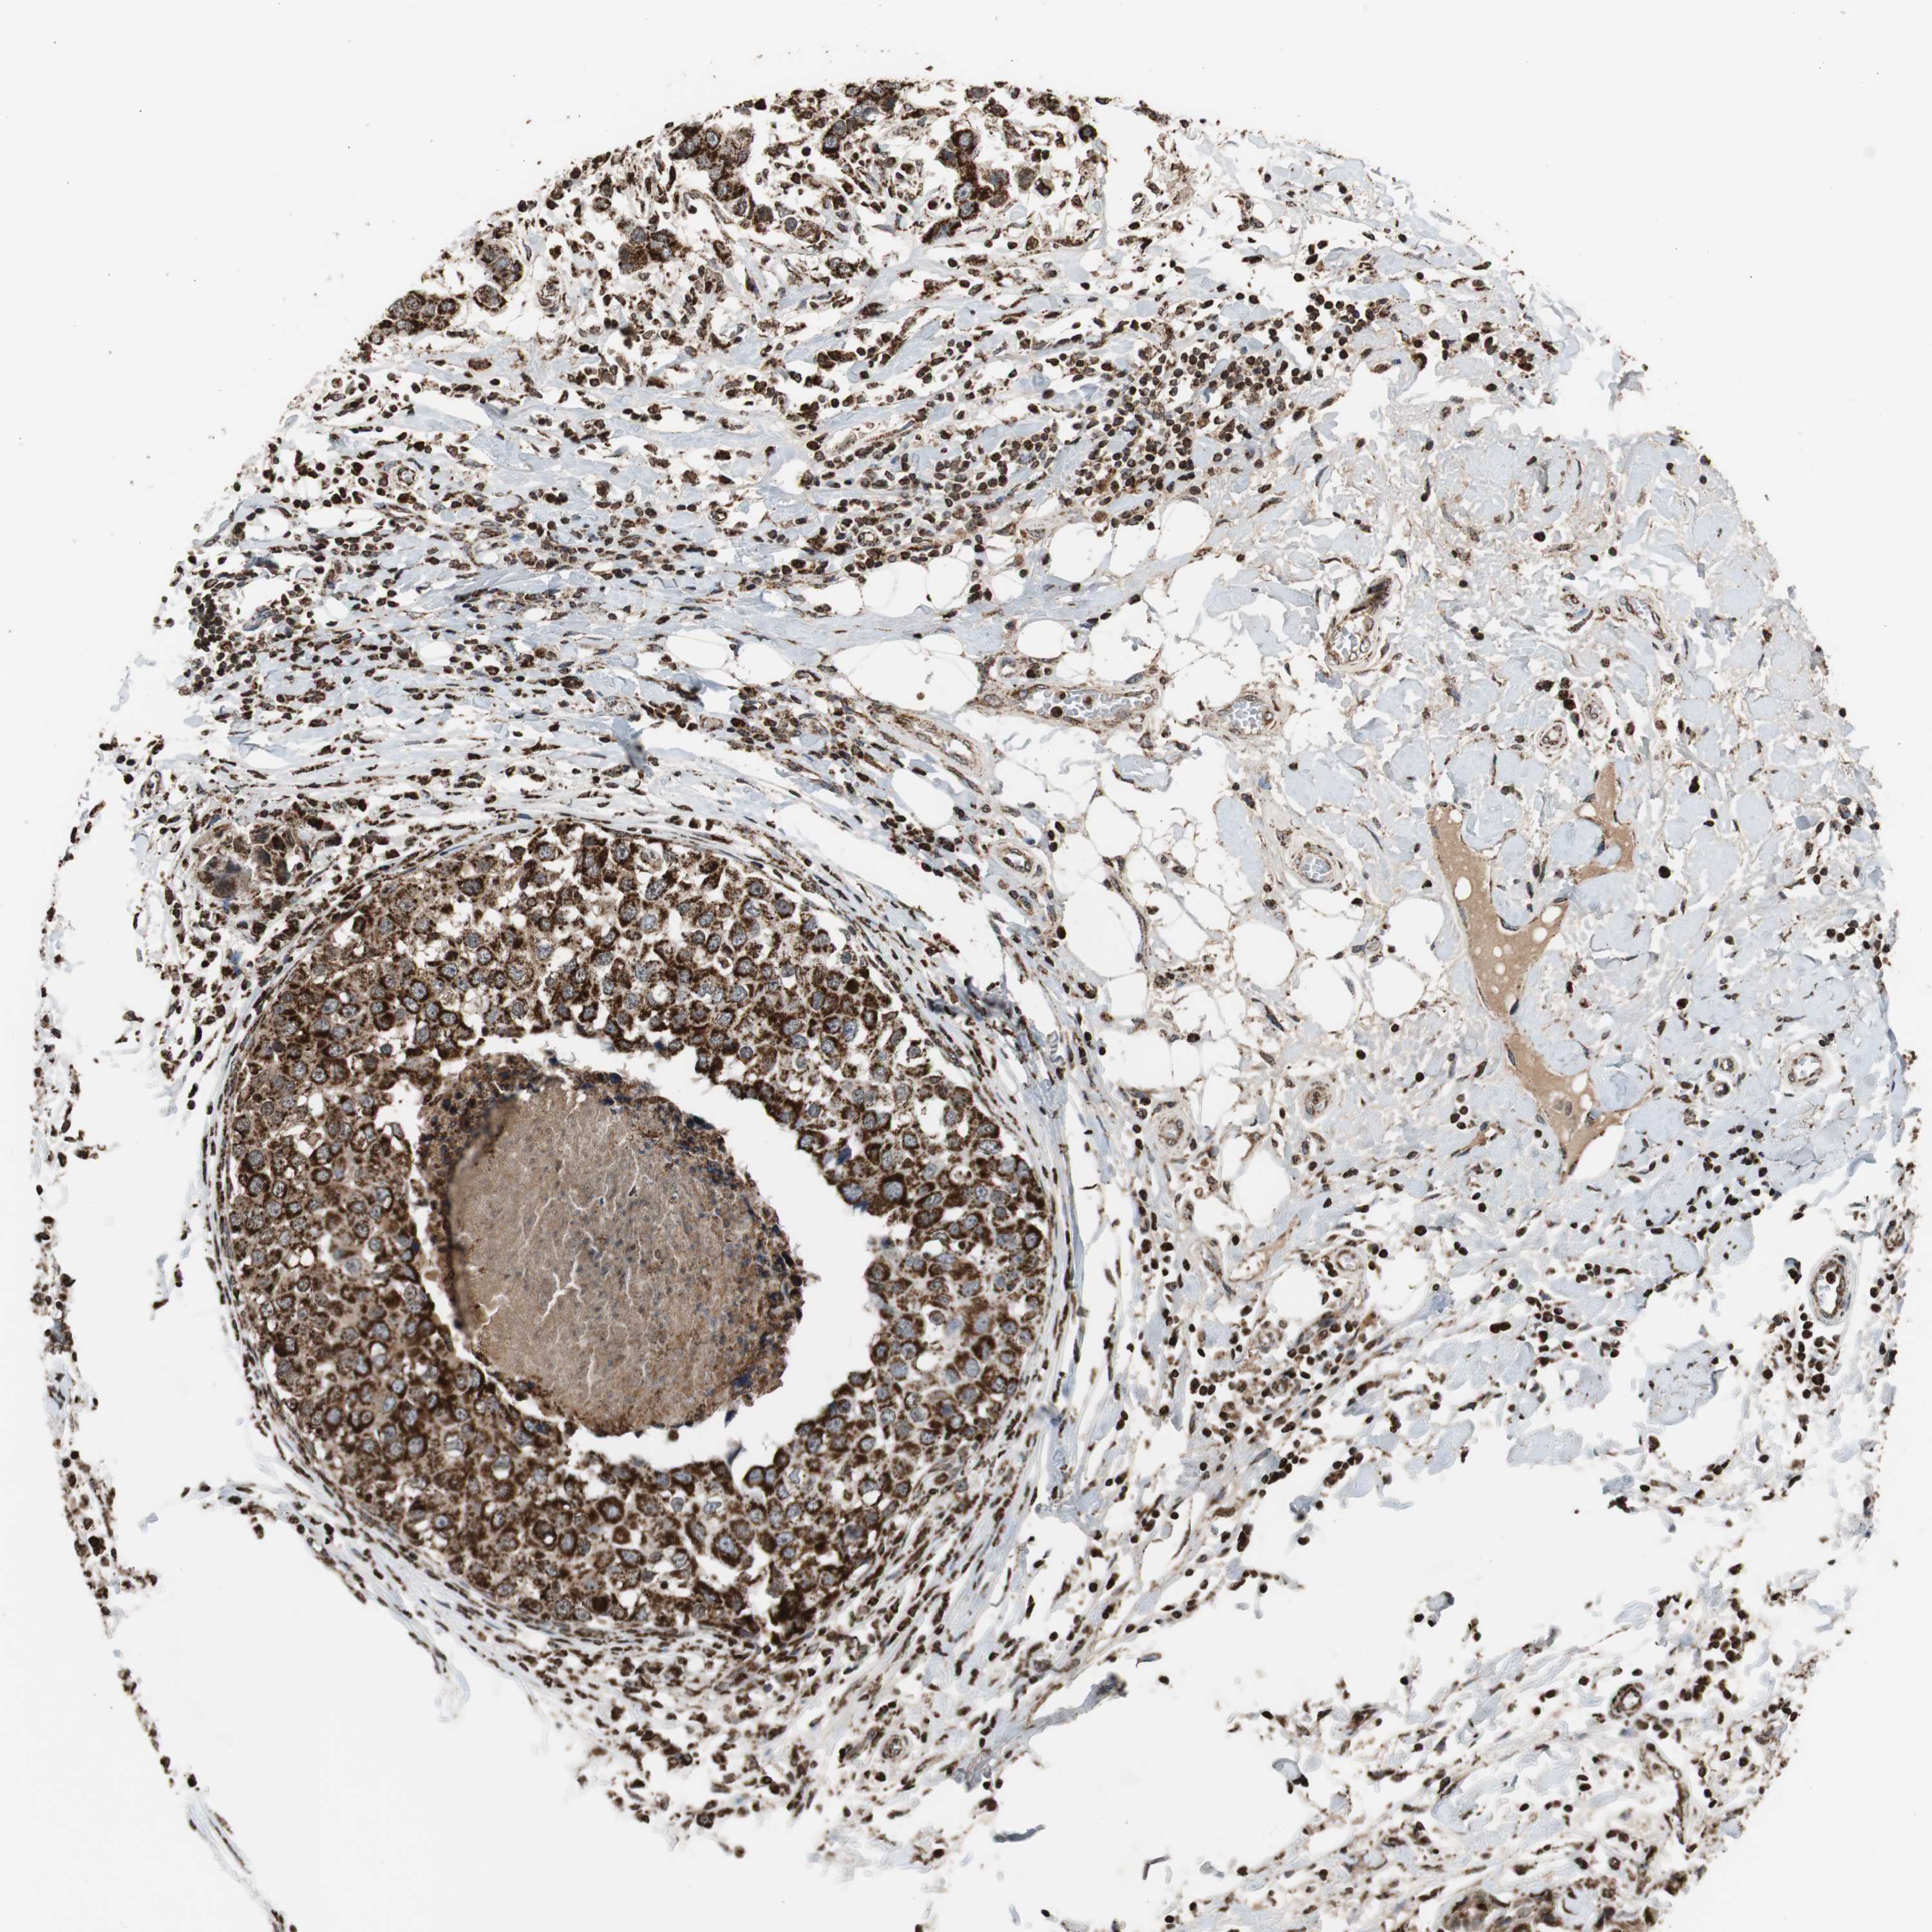

CANCER BREAST CANCER Show tissue menu

BRCA TCGA BRCA VALIDATION PROTEIN EXPRESSION